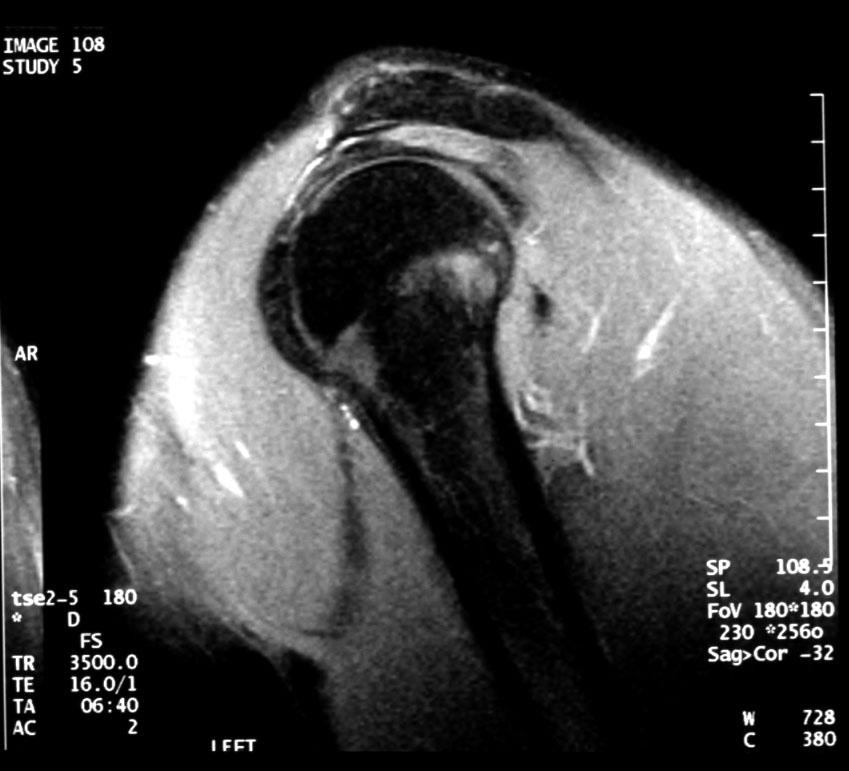

Normal MR of Left Shoulder (lateral saggital) -- Identify: humerus, acromion,

supraspinatus muscle